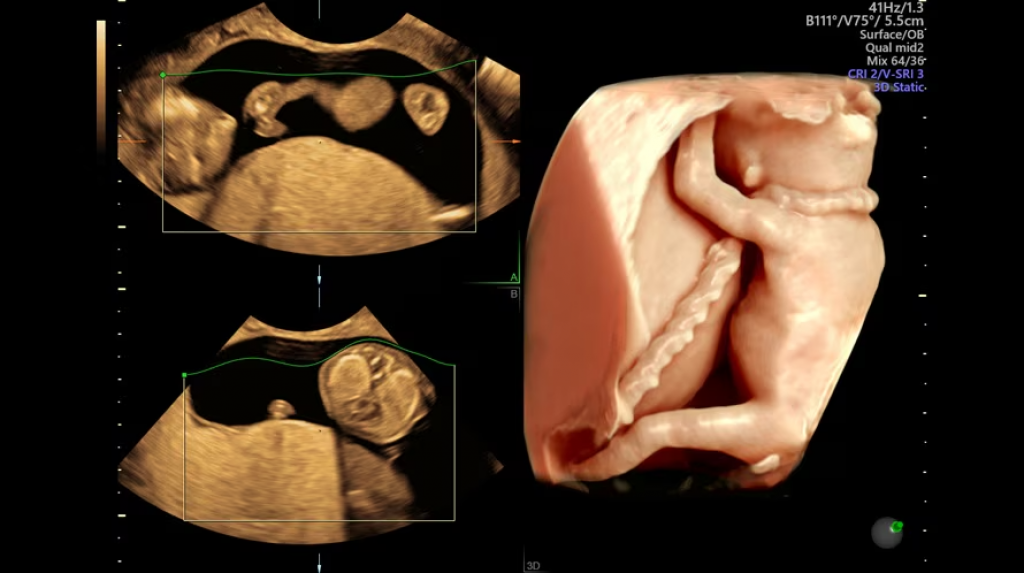

HDlive, HDlive Silhouette e HDlive Studio per una rappresentazione anatomica realistica

SonoRender per volumi 3D definiti e uniformi

Rendering 3D/4D ad alta fedeltà

Diagnostica fetale avanzata